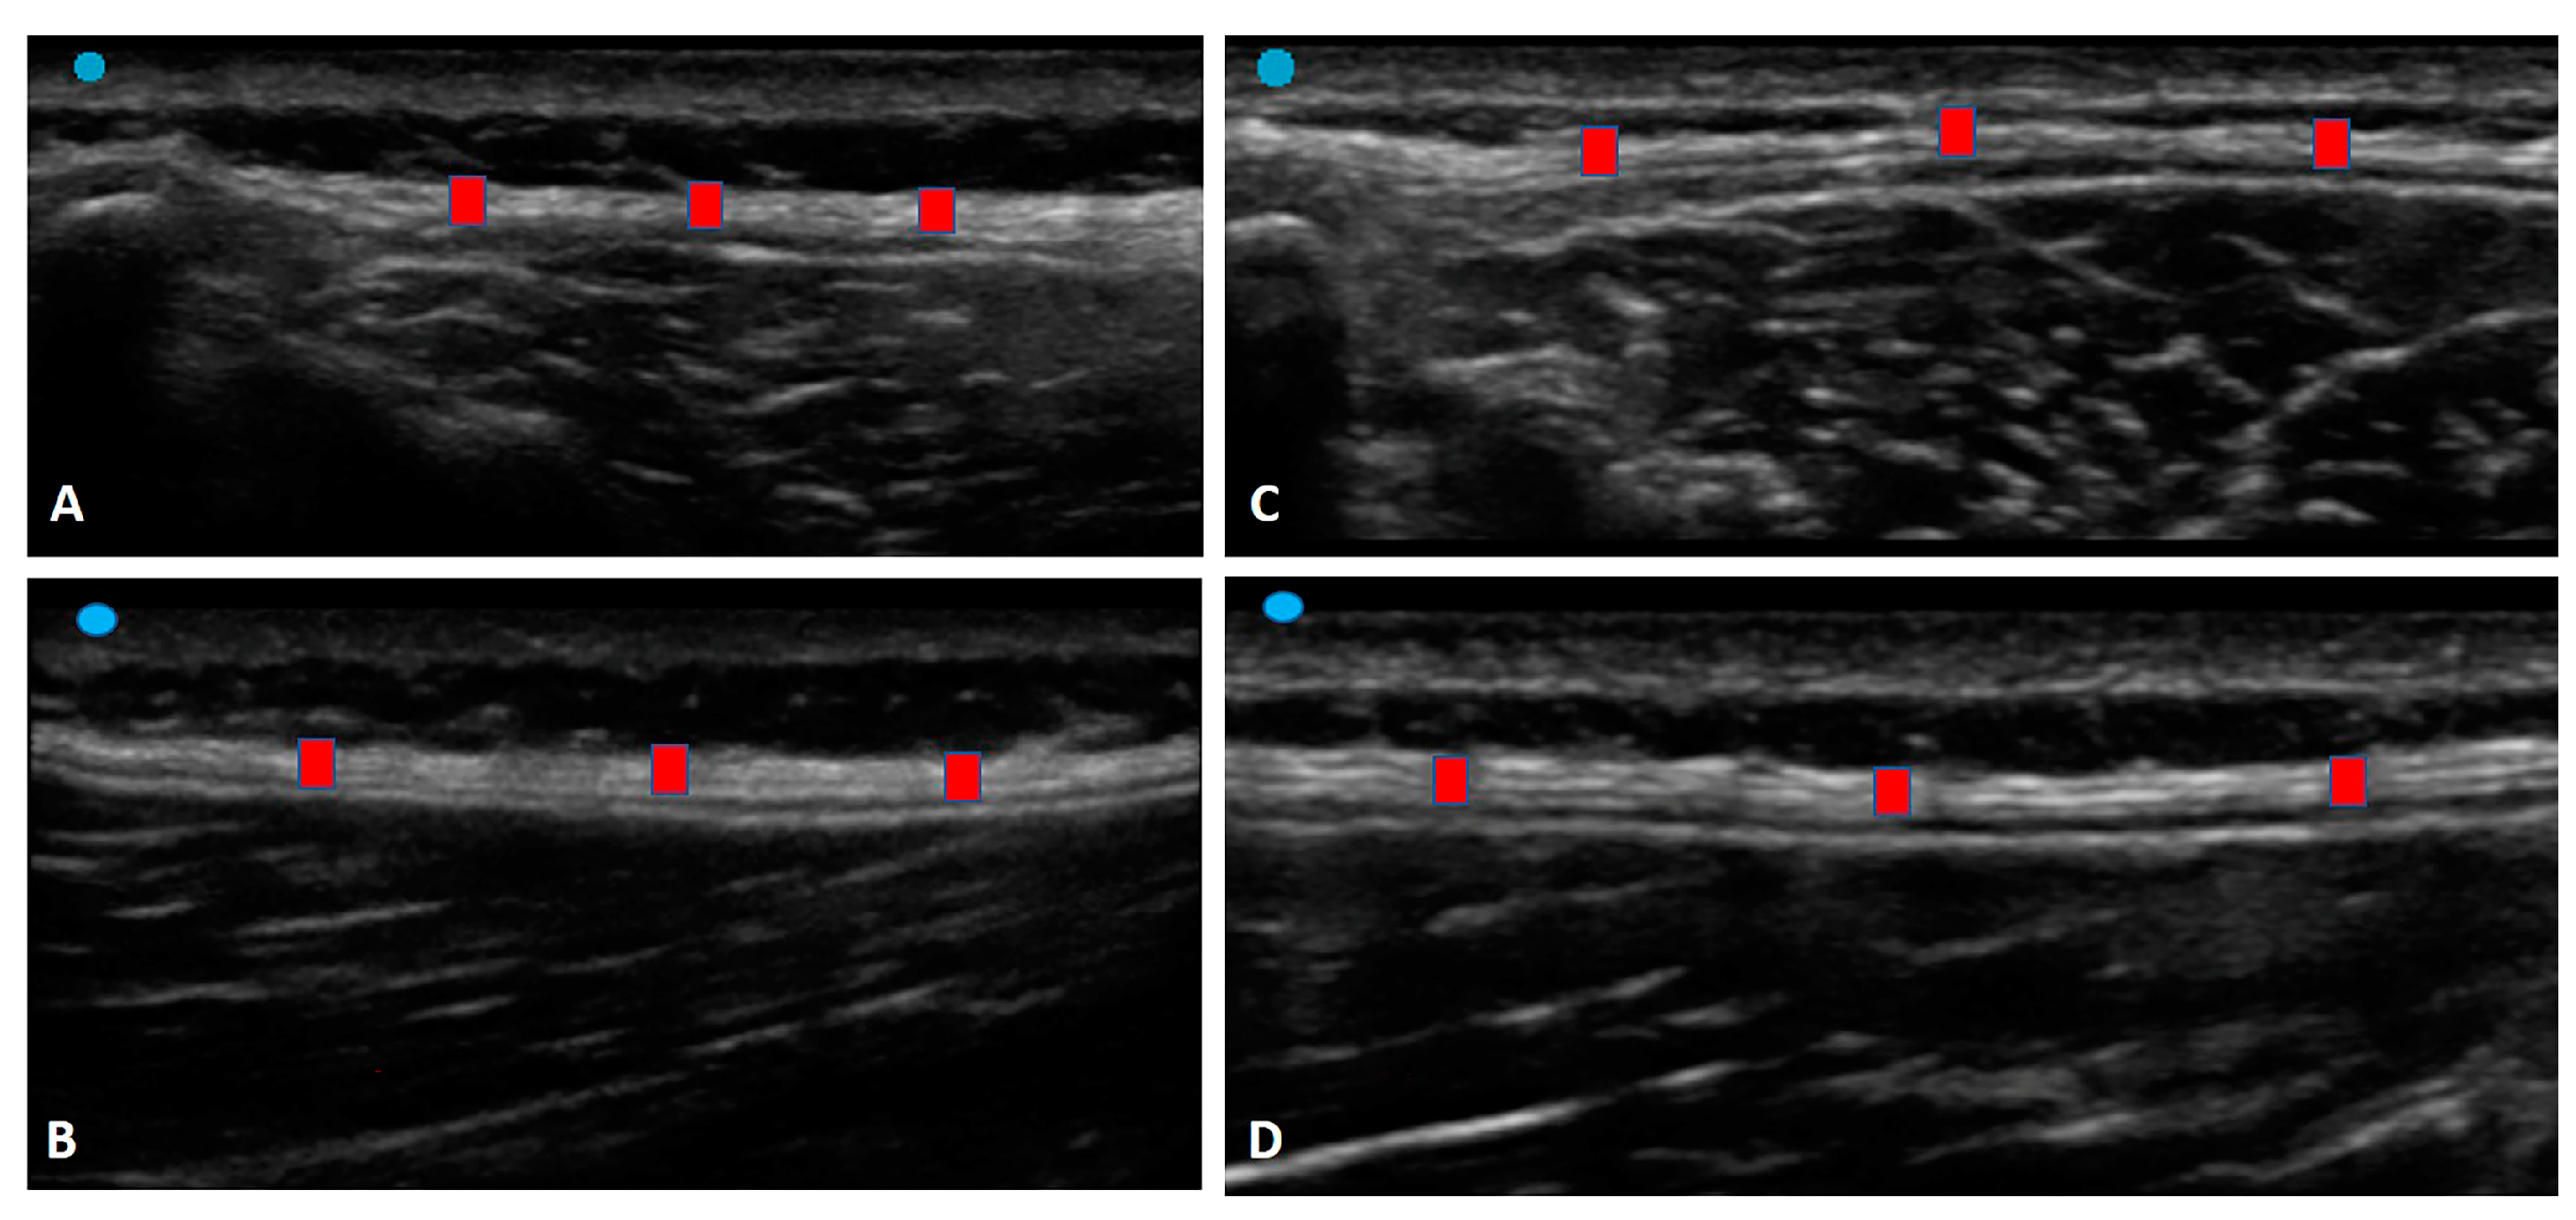

The study’s primary aim was to investigate the difference in the TLF thickness at the L3 level of the lumbar spine in chronic non-specific LBP patients compared with healthy volunteers. An analysis of our results on the TLF thickness showed that in group 1, at the longitudinal and transverse axes, it was thicker (long. = 2.20 ± 0.8 mm; transv.: 2.10 ± 0.61 mm) (Table 2) than group 2 (long. = 1.90 ± 0.8 mm; transv.: 1.65 ± 0.45 mm) (Table 3), showing statistical differences (Table 4, Figure 4).

Figure 4.

Ultrasound images of the TLF thickness: (A) Group 1: transverse axis; (B) Group 1: longitudinal axis; (C) Group 2: transverse axis; (D) Group 2: longitudinal axis. Red square: TLF.

In light of these findings, the TLF tends to be thicker in the chronic non-specific LBP patients. It remodeled over time in response to repetitive stresses created by pre-existing altered movement patterns due to repetitive motion, habitual posture, and sports [13]. Moreover, the TLF playing an important role in myofascial force transmission [14] can easily change in terms of stiffness and movement impairment, remodelling itself in debilitated tissue that is densified and fibrotic. These results have confirmed, as has been demonstrated by other studies [13,14,15], that in chronic LBP, microinjury and/or inflammation influence nociceptor activation and body movement patterns through a series of interrelated mechanisms that also include aberrant afferent input and maladaptive tissue remodelling [32].

In addition, statistically significant differences in the TLF thickness were evident between the longitudinal and transverse axes within group 2 for both sides (Group 2 Left long. vs. Group 2 Left transv.: p = 0.001; Group 2 Right long. vs. Group 2 Right transv.: p = 0.02) (Table 4). Pirri et al. [27] showed that expertise in US imaging and identifying anatomical landmarks from a fascial point of view is fundamental, as is the position of the probe and the type of axis; for this reason, we decided to create this protocol for the TLF. Indeed, the latter has a specific basal tension in physiological conditions which lets it perceive the contraction of the underlying muscles due to local mechanoreceptors. This effect permits us to perceive the lateral transmission of force. An alteration to the viscoelastic features of the TLF, which is anatomically in contiguity with it, can modify the field lines of traction within the fascial tissue, creating an alteration in its basal tension. Possibly, we hypothesize that these differences between the longitudinal and transverse axes are evident in healthy volunteers due to normal fascial adaptation to the lateral transmission of force, while in chronic non-specific LBP patients, fascial remodelling creates a situation of blockage of the normal movement with a decrease in fascial adaptation, maintaining the same thickness in the two axes.

Moreover, these findings extend those about the anisotropic behavior of fasciae [33], confirming how a healthy TLF has a good adaptive capacity that is different in multiple directions of movement [34]. According to our data, the patients with chronic non-specific LBP lost TLF anisotropy, with it becoming homogeneously thicker. The aponeurotic fasciae, as with the TLF, are usually more rigid in the longitudinal direction, working as a tendon, connecting different body segments and different muscles, and being more adaptable in the transversal direction [34]. This behavior allows the adaptability of the fasciae to the volume variation of the underlying muscles. In our patients, the US evaluation suggests that the TLF lost this anisotropic behavior, with it becoming thicker and rigid in both directions, a sort of “frozen back”.